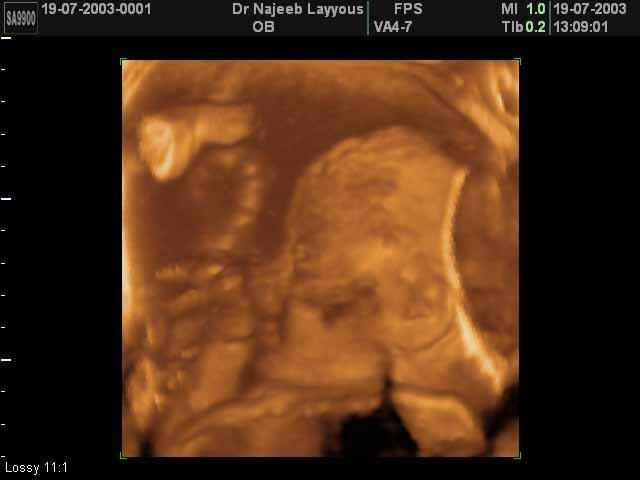

صور جانبية لرأس الجنين بجهاز الالتراساوند ثلاثي الأبعاد | الدكتور نجيب ليوس